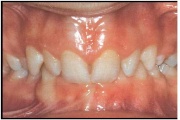

Valehambumus

Hammaste asendianomaaliad on tingitud tavaliselt arenguhäirest.

Sümptomid:

probleemid kõnega

probleemid neelamisega

suuhingamine